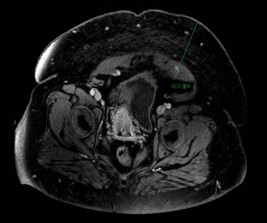

患者女性,身高156cm,体重145kg,BMI高达59.6,属于极度肥胖体型。患者合并贫血、支气管哮喘、心肺功能欠佳等多种慢性病,同时存在盆腔粘连、骨盆狭窄等情况,下腹壁脂肪层极厚,不仅增加麻醉与围手术期风险,也为手术操作带来了极大困难。该患者子宫及肿瘤横径超20cm,占据整个盆腔,下腹壁脂肪堆积腹壁厚度超过10cm。患者先后就诊于省内多家医院均未能手术,遂转诊我院。